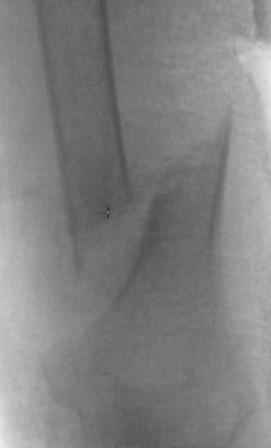

Уважаемые коллеги. Хочу продемонстрировать пример к недавней дискуссии о способности плечевой кости срастаться без операции.

Пациентка 87 лет, деменция, соматически сохранна. Конечность после травмы фиксирована в циркулярной бесподкладочной гипсовой повязке. Через месяц выявлена рана, образовавшаяся вседствие перфорации кожи острым концом дистального фрагмента. Далее - гипсовая лонгета и перевязки дома сиделкой. Через 2 месяца после травмы констатирована консолидация. По поводу концевого остеомиелита выполнена экономная резекция плечевой кости с ушиванием раны наглухо, заживление первичное.